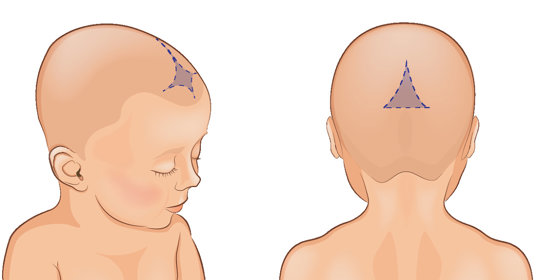

產後掉髮:原因、症狀和有效應對方法